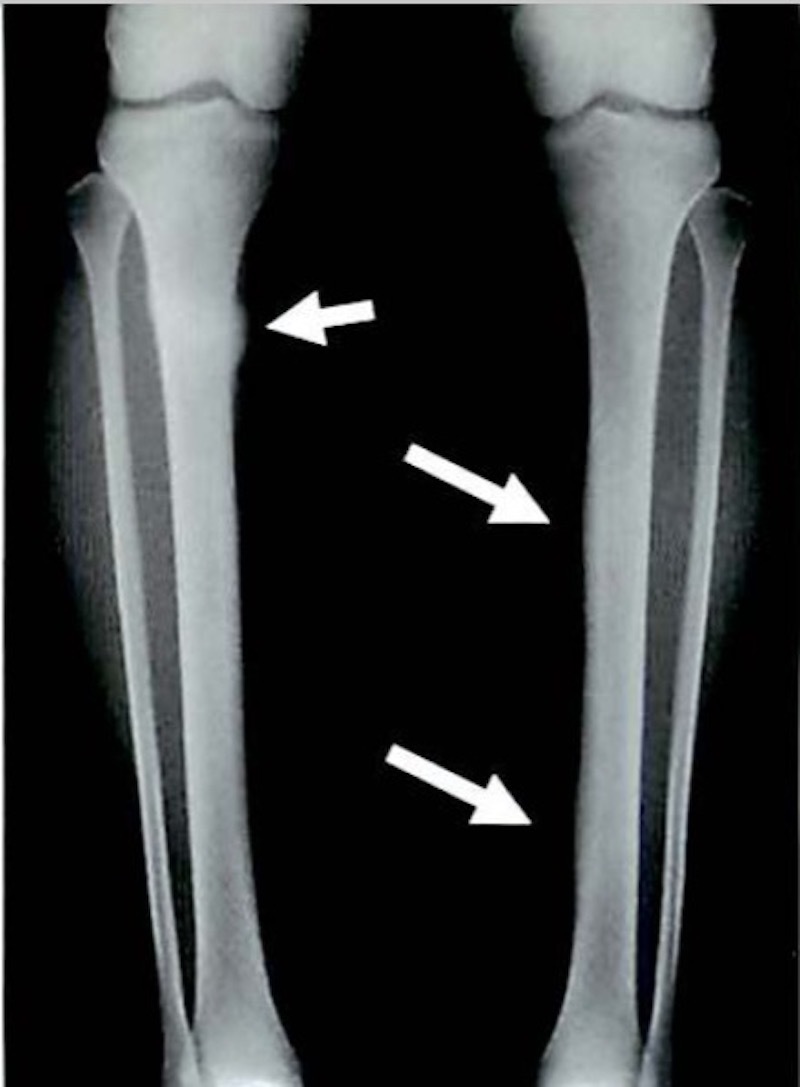

疲労骨折は健常な骨において同一部位に

外力が繰り返されることによって

骨が疲弊し起こる骨折です。

突然起きる骨折とは異なり、ジャンプや

ダッシュなどの通常のスポーツにより

繰り返される外力が骨に微細な骨折

を潜在的に引き起こします。

初期は骨がストレスに反応して骨吸収像を呈し

経過するに従い骨吸収と骨新生が

複雑に並存した状態に進んでいきます。

つまり繰り返す弱い力により骨に小さな骨折

が引き起こされ、その状態が慢性的に

続くことで大きな骨折に発展します

スポーツの種類により

肋骨(剣道)、頚椎(ゴルフ)

尺骨(バレー、ソフトボール)、恥骨(卓球)

脛骨(長距離走、走高跳など)

腓骨(長距離走)、中足骨(短距離走)

などが疲労骨折の好発部位となります。

※ Monthly orthopaedicsから画像抜粋